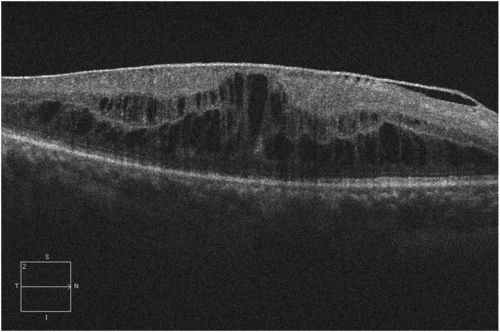

Within recent years, OCT has quickly become an important ancillary procedure in diagnosing and treating DME. Three basic structural changes can be seen on OCT: retinal swelling, cystoid macular edema, and subretinal fluid (Figure 4). Macular scans can quickly and accurately identify even subtle areas of thickening, along with quantitative metrics for different areas. Changes in the anatomic distribution of DME can be monitored over time, especially the fluid’s relationship to the fovea. This information has clinical and research implications for the evaluation and management of DME. The International Council of Ophthalmology's guidelines for diabetic eye care, published in 2018, adopted the clinical entities of center-involved DME (ci-DME) and non-center–involved DME (non-ciDME) for the evaluation of macular fluid (Figure 5), as follows:

- Disorganization of the retinal inner layers (DRIL) is thought to represent damaged cells within the inner retinal layers, indicating a disruption in the normal visual pathway from the photoreceptors to the ganglion cells.[24] DRIL is identified on OCT when there is disruption of the demarcating interface lines between the ganglion cell-inner plexiform complex, inner nuclear layer (INL), outer plexiform layer (OPL), and outer nuclear layer. Eyes with DRIL have a worse baseline and final VA despite anti–vascular endothelial growth factor (VEGF) injections and have an almost 8× greater risk for poor visual recovery. In contrast, the resolution of DRIL results in better visual outcomes (Figure 6).[25][26][27] DRIL was better correlated with VA than either glycemic status and CST.[24]

- DME associated with VMIA, notably ERM and VMT, has poorer visual outcomes (Figure 8).[34][35] VMIA have been observed in 7%–16% of eyes with DME, with an annual incidence rate of up to 4.5%.[36][37] The READ-3 trial showed that eyes with VMIA still had a good response to anti-VEGF therapy.[38] Presence of posterior vitreous detachment (PVD) has been associated with improved visual outcomes. Nasrallah et al. reported that DME was present in 55% of eyes with an attached hyaloid, compared with only 20% of eyes with PVD.[39] Hikishi et al. reported only a 25% rate of spontaneous resolution in eyes with attached posterior hyaloid, vs a 55% resolution rate in eyes with PVD.[40] The role of the vitreous and VMIA in DME, which may be related to changes in transvitreal oxygenation, hyalocyte proliferation from vitreous remnants on the ILM, and the present growth factors in the premacular hyaloid, is still being investigated.[41][42][43][44]